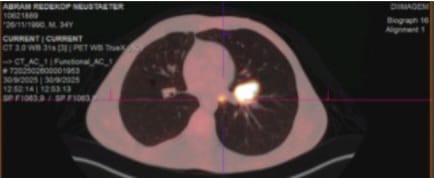

A new update on Abram He never got to implant his jawbone because he has three new tumors which you can find in the picture gallery. One on the other side jawbone, one on his chest one in his lung,He is now taking chemotherapy. in Brazil. ABRAM and his wife and family are in urgent need of our prayers and support. May God bless every prayer and support